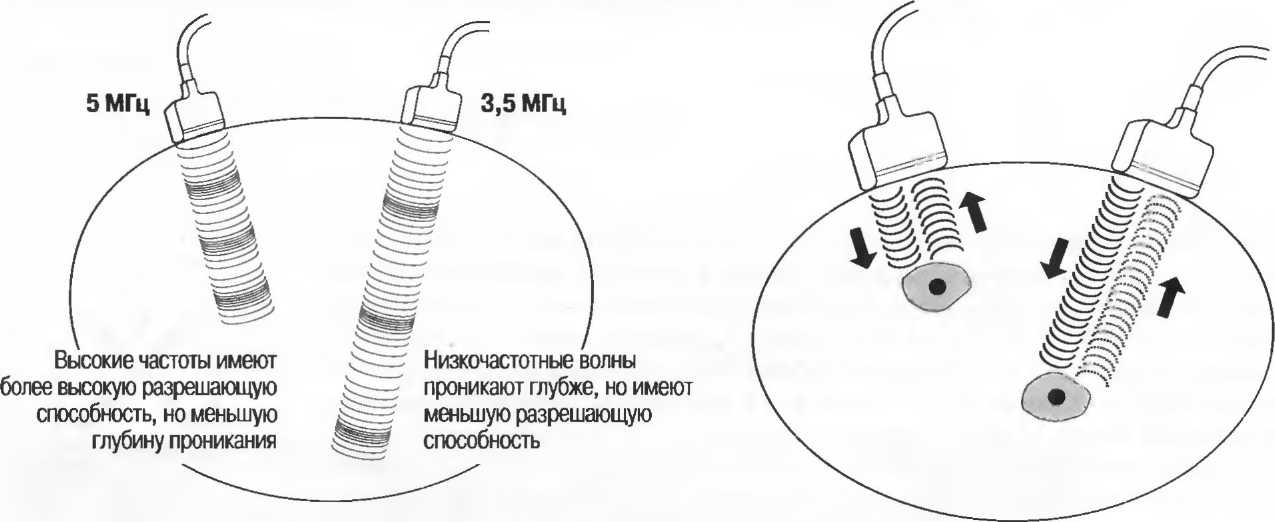

Затухание

Ткани тела поглощают и рассеивают ультразвук по-разному. Высокие частоты поглощаются и рассеиваются (гасятся) в большей степени, чем низкие. Поэтому, чтобы достичь более глубоких тканей, необходимо использовать более низкие частоты, так как менее вероятно, что эти волны затеряются при прохонодении через ткани. На практике оптимально использовать частоту около 3,5 МГц для глубокого сканирования у взрослых и частоту 5 МГц и выше для исследования более худых пациентов или детей. Частота 5 МГц и выше используется для исследования поверхностных органов у взрослых.

Высокие частоты дают более детальное изображение, но имеют меньшую проникающую способность.

Частота и разрешающая способность

Чем выше частота ультразвукового излучения, тем выше разрешающая способность. Это означает, что при использовании более высокой частоты возможна визуализация более мелких структур. Одновременно проникающая способность ультразвуковой волны в ткани становится меньше. Сканирование, таким образом, является компромиссом; при этом используется максимально высокая частота, достаточная для проникновения на заданную глубину (рис. 11).